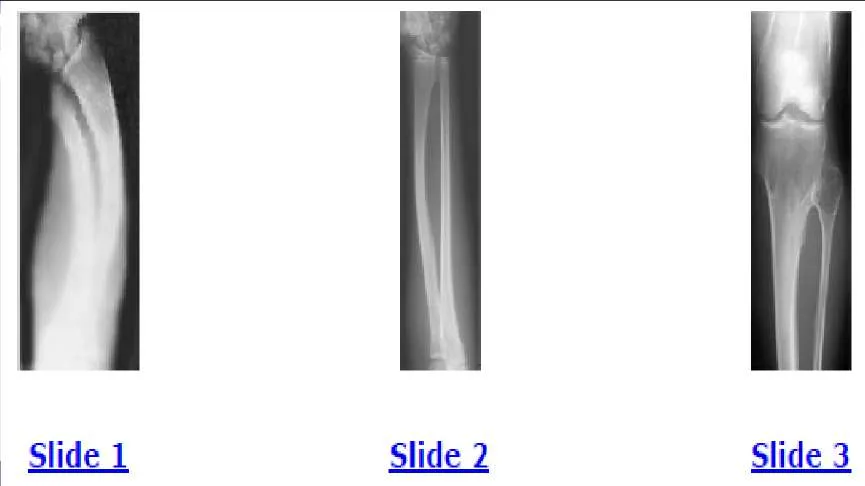

A 12-year-old boy is brought to the clinic by his concerned parents. The boyâ s forearm is bowed, and his parents are confused as to the possible diagnosis and treatment options. You notice that the right forearm of the child is bowed ulnarwards and is shorter compared to the left forearm. The pronosupination is markedly decreased on the right side but is also limited on the left side. The patient has a good grip, pinch, and grasp. He is neurologically intact as well. The parents say that they first noticed the deformity around 6 or 7 years ago, and the mother informs you that she had noticed a hard bump on the forearm. She has recently noticed another bump on his right leg. The child does not complain of pain and is using both of his hands quite well. The parents were informed by a previous physician that the child has Madelungs deformity and are concerned that the disease is now involving other areas of his body. An immediate appointment for magnetic resonance imagine (MRI) and computed tomography (C T) scan are not available, and a genetic evaluation has been carried out previously. As you await the report from the geneticist office, you decide to get a skeletal radiograph series on the patient. The radiograph of the opposite forearm (Slide 1) and right leg are shown (Slide 2). You order a radiograph of the forearm. The anteroposterior radiograph is shown (Slide 3). Your suspected diagnosis is:

Diaphyseal achalasia, also called multiple hereditary exostoses, classically presents in a young individual with multiple sites of involvement. The more involved the disease, the more likely hand involvement becomes. Forearm involvement is also common. The radius is bowed due to the shortened ulna. The risk of radial head dislocation is higher if the radius does not bow. While infection or traumatic injury could have produced early physeal arrest as seen in the first radiograph, presence of lesions elsewhere indicates multiple hereditary exostoses and should be investigated with skeletal surveys. Multiple epiphyseal dysplasia is not a possible diagnosis as only the ulna is involved in the first radiograph and radius alone in the left forearm. No enchondromas are present.

A 12-year-old boy is brought to the clinic by his concerned parents. The boys forearm is bowed, and his parents are confused as to the possible diagnosis and treatment options. You notice that the right forearm of the child is bowed ulnarwards and is shorter compared to the left forearm. The pronosupination is markedly decreased on the right side but is also limited on the left side. The patient has a good grip, pinch, and grasp. He is neurologically intact as well. The parents say that they first noticed the deformity around 6 or 7 years ago, and the mother informs you that she had noticed a hard bump on the forearm. She has recently noticed another bump on his right leg. The child does not complain of pain and is using both of his hands quite well. The parents were informed by a previous physician that the child has Madelungs deformity and are concerned that the disease is now involving other areas of his body. You order a radiograph of the forearm. The anteroposterior radiograph is shown (Slide 1). The childâ s skeletal radiograph survey is also presented (Slide 2 and Slide 3). The genetic pattern seen in patients with this type of presentation is:

Explanation:

A 12-year-old boy is brought to the clinic by his concerned parents. The boy s forearm is bowed, and his parents are confused as to the possible diagnosis and treatment options. You notice that the right forearm of the child is bowed ulnarwards and is shorter compared to the left forearm. The pronosupination is markedly decreased on the right side but is also limited on the left side. The patient has a good grip, pinch, and grasp. He is neurologically intact as well. The parents say that they first noticed the deformity around 6 or 7 years ago, and the mother informs you that she had noticed a hard bump on the forearm. She has recently noticed another bump on his right leg. The child does not complain of pain and is using both of his hands quite well. The parents were informed by a previous physician that the child has Madelungs deformity and are concerned that the disease is now involving other areas of his body. You order a radiograph of the forearm. The anteroposterior radiograph is shown (Slide 1). The childâ s skeletal radiograph survey is also presented (Slide 2 and Slide 3). Which of the following areas is unlikely to be involved:

The clavicle is a membranous bone, and osteochondromas do not arise in membranous bones.

A 12-year-old boy is brought to the clinic by his concerned parents. The boyâ s forearm is bowed, and his parents are confused as to the possible diagnosis and treatment options. You notice that the right forearm of the child is bowed ulnarwards and is shorter compared to the left forearm. The pronosupination is markedly decreased on the right side but is also limited on the left side. The patient has a good grip, pinch, and grasp. He is neurologically intact as well. The parents say that they first noticed the deformity around 6 or 7 years ago, and the mother informs you that she had noticed a hard bump on the forearm. She has recently noticed another bump on his right leg. The child does not complain of pain and is using both of his hands quite well. The parents were informed by a previous physician that the child has Madelungâ s deformity and are concerned that the disease is now involving other areas of his body. You order a radiograph of the forearm. The anteroposterior radiograph is shown (Slide 1). The childâ s skeletal radiograph survey is also presented (Slide 2 and Slide 3). The chance of hand involvement in this child is:

The hand is involved in 30% to 80% of cases.

A 12-year-old boy is brought to the clinic by his concerned parents. The boyâ s forearm is bowed, and his parents are confused as to the possible diagnosis and treatment options. You notice that the right forearm of the child is bowed ulnarwards and is shorter compared to the left forearm. The pronosupination is markedly decreased on the right side but is also limited on the left side. The patient has a good grip, pinch, and grasp. He is neurologically intact as well. The parents say that they first noticed the deformity around 6 or 7 years ago, and the mother informs you that she had noticed a hard bump on the forearm. She has recently noticed another bump on his right leg. The child does not complain of pain and is using both of his hands quite well. The parents were informed by a previous physician that the child has Madelungs deformity and are concerned that the disease is now involving other areas of his body. You order a radiograph of the forearm. The anteroposterior radiograph is shown (Slide 1). The childâ s skeletal radiograph survey is also presented (Slide 2 and Slide 3). The most likely complication in this child is:

Ulnar carpal translocation occurs due to the steep radial articular angulation that occurs due to the tethering effect of a shortened ulna and is already apparent in early stages in the first radiograph. While peroneal palsy is possible due to a proximal fibula lesion, it is less common. Malignant transformation occurs, risk varies with families.

A 12-year-old boy is brought to the clinic by his concerned parents. The boys forearm is bowed, and his parents are confused as to the possible diagnosis and treatment options. You notice that the right forearm of the child is bowed ulnarwards and is shorter compared to the left forearm. The pronosupination is markedly decreased on the right side but is also limited on the left side. The patient has a good grip, pinch, and grasp. He is neurologically intact as well. The parents say that they first noticed the deformity around 6 or 7 years ago, and the mother informs you that she had noticed a hard bump on the forearm. She has recently noticed another bump on his right leg. The child does not complain of pain and is using both of his hands quite well. The parents were informed by a previous physician that the child has Madelungs deformity and are concerned that the disease is now involving other areas of his body. You order a radiograph of the forearm. The anteroposterior radiograph is shown (Slide 1). The childâ s skeletal radiograph survey is also presented (Slide 2 and Slide 3). The difference between Madelungâ s deformity and this boyâ s condition is:

The ulna is elongated or dorsally subluxed in Madelung's deformity.

A 12-year-old boy is brought to the clinic by his concerned parents. The boys forearm is bowed, and his parents are confused as to the possible diagnosis and treatment options. You notice that the right forearm of the child is bowed ulnarwards and is shorter compared to the left forearm. The pronosupination is markedly decreased on the right side but is also limited on the left side. The patient has a good grip, pinch, and grasp. He is neurologically intact as well. The parents say that they first noticed the deformity around 6 or 7 years ago, and the mother informs you that she had noticed a hard bump on the forearm. She has recently noticed another bump on his right leg. The child does not complain of pain and is using both of his hands quite well. The parents were informed by a previous physician that the child has Madelungs deformity and are concerned that the disease is now involving other areas of his body. You order a radiograph of the forearm. The anteroposterior radiograph is shown (Slide 1). The childâ s skeletal radiograph survey is also presented (Slide 2 and Slide 3). All of the following are acceptable options, either alone or in combination, for management of this childâ s condition, except:

Although hemiphyseal stapling is an acceptable option to correct radial articular angulation, in this boy the distal radial physis is already fused as is seen in the first radiograph.

A 12-year-old boy is brought to the clinic by his concerned parents. The boys forearm is bowed, and his parents are confused as to the possible diagnosis and treatment options. You notice that the right forearm of the child is bowed ulnarwards and is shorter compared to the left forearm. The pronosupination is markedly decreased on the right side but is also limited on the left side. The patient has a good grip, pinch, and grasp. He is neurologically intact as well. The parents say that they first noticed the deformity around 6 or 7 years ago, and the mother informs you that she had noticed a hard bump on the forearm. She has recently noticed another bump on his right leg. The child does not complain of pain and is using both of his hands quite well. The parents were informed by a previous physician that the child has Madelungs deformity and are concerned that the disease is now involving other areas of his body. You order a radiograph of the forearm. The anteroposterior radiograph is shown (Slide 1). The childâ s skeletal radiograph survey is also presented (Slide 2 and Slide 3). Which of the following is not true regarding the possibility of malignant degeneration in this child:

Bone scan cannot differentiate between an active lesion and a malignant transformation.